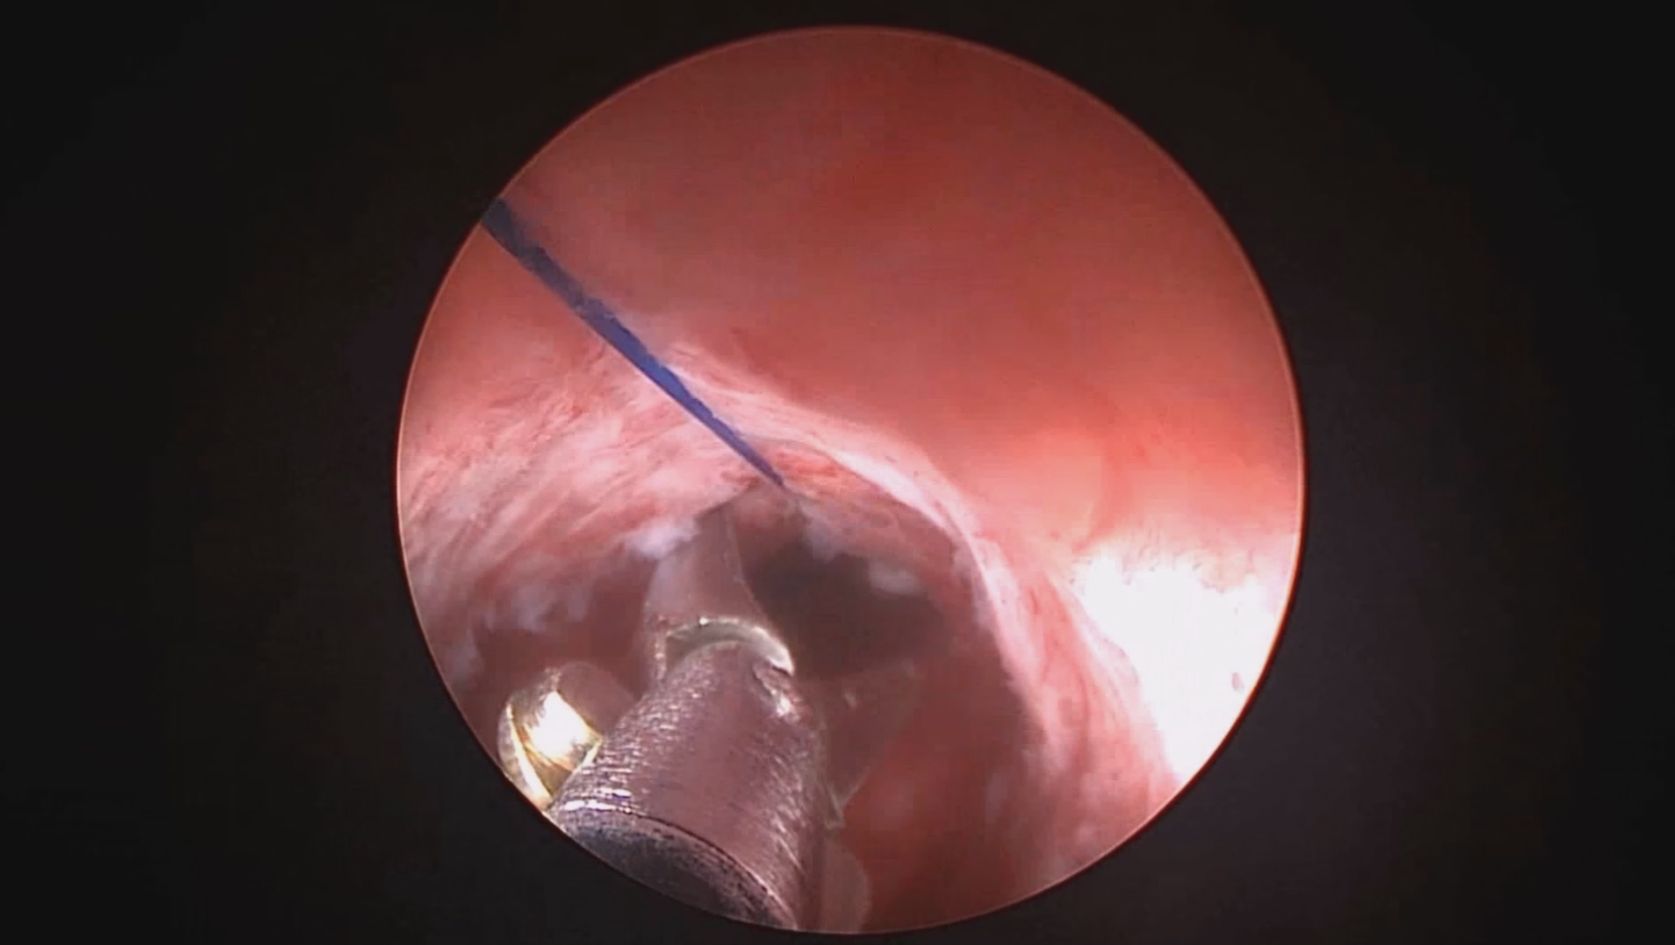

患者39岁,G4P2,顺产2次。2025年2月因异常子宫出血,阴道出血淋漓不净1+月行宫腔镜检查及内膜活检,病检为子宫内膜增生(无非典型)伴息肉形成。2025年3月,行经第3天,月经量大伴腹痛,要求放置曼月乐并固定。宫腔镜见内膜杂乱,脱落不全,吸刮内膜送病检,4-0不可吸收线将曼月乐环缝合固定于宫腔上段后壁。术中打结、推结很困难,放弃打结,留较长线尾在宫颈管,必要时可牵拉线尾调整节育环位置,只要缝合到子宫肌层,肌肉的卡压阻力可以起到固定作用,继续探索不用打结推结的固定方法。术后多次复查B超,子宫偏大,7.7cm*6.6cm*7.8cm,环顶端距宫底3cm。